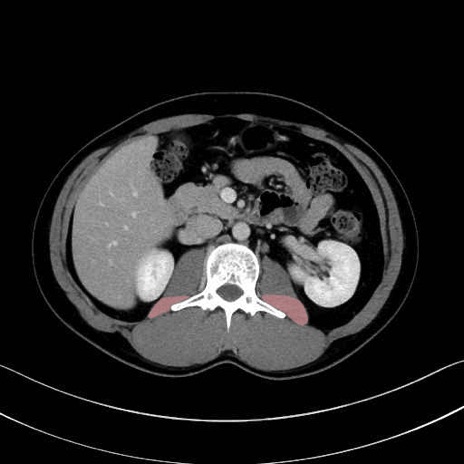

腰方形筋(quadratus lumborum muscle)のCT画像の解剖

腰方形筋 (Quadratus lumborum)

2. 腸腰筋群と骨盤底筋

大腰筋 (Psoas major)